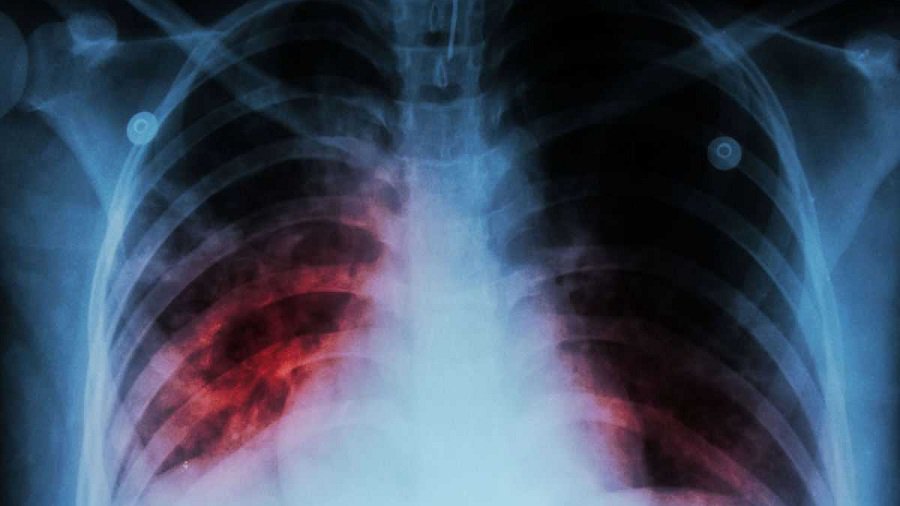

Вакцина против туберкулеза оказалась эффективнее, чем считалось

Вакцину БЦЖ (BCG, сокращ. «бацилла Кальметта — Герена») ученые впервые создали в 1920-х годах, но она до сих пор остается важнейшим средством профилактики тяжелых осложнений туберкулеза. По данным Всемирной организации здравоохранения, во всем мире эту вакцину получают около 100 миллионов детей ежегодно.